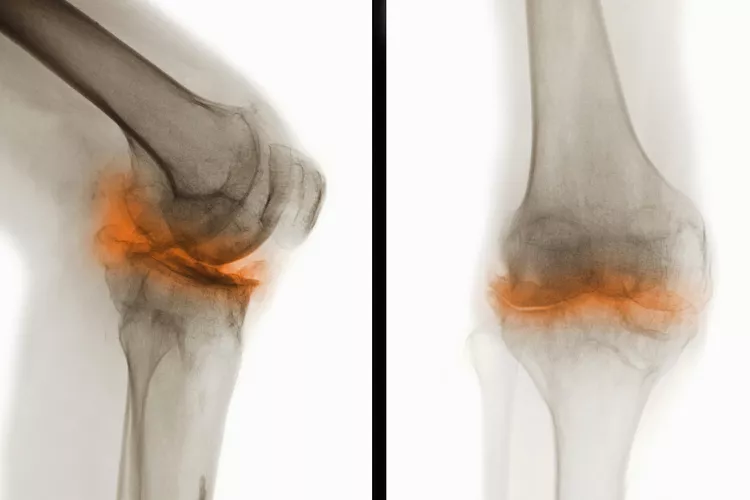

骨關(guān)節炎(Osteoarthritis, OA),一種常見(jiàn)的慢性關(guān)節疾病,主要特征是關(guān)節軟骨退化和關(guān)節邊緣骨質(zhì)增生。隨著(zhù)病情進(jìn)展,骨關(guān)節炎不僅會(huì )導致關(guān)節疼痛和功能受限,還可能引發(fā)一系列并發(fā)癥,影響患者的整體健康和生活質(zhì)量。

在骨關(guān)節炎(OA) 中,覆蓋骨頭末端并幫助骨頭相互滑動(dòng)的光滑軟骨會(huì )逐漸磨損。這會(huì )導致骨頭相互摩擦和磨擦。

年齡、受傷和重復運動(dòng)都可能導致骨關(guān)節炎,但最常見(jiàn)的原因是正常的磨損,尤其是在50歲以后。它可以發(fā)生在任何關(guān)節上,但最常見(jiàn)于手、膝蓋、臀部和脊柱。

骨關(guān)節炎是一種慢性疾病。骨關(guān)節炎無(wú)法治愈。一旦軟骨破裂,它就不會(huì )自行再生。隨著(zhù)時(shí)間的推移,您可能會(huì )因患有骨關(guān)節炎而出現其他問(wèn)題或并發(fā)癥。